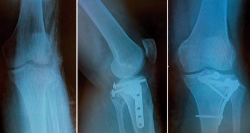

En 1979, Schatzker(1) (Figura 1) describe por primera vez una clasificación de las fracturas de la meseta tibial que divide en 6 tipos (I-VI). Los tipos I-II-III se consideran fracturas de “baja” energía y los IV-V-VI de “alta” energía. Cabe reseñar que esta se establecía en función de estudios realizados con radiografía simple, especialmente en el plano anteroposterior. No existe una evaluación tridimensional de la fractura y, por tanto, no hace mención de fracturas en el margen posterior de la meseta tibial. Según su experiencia personal sobre una serie de 94 pacientes, llama la atención el alto porcentaje de fracturas de tipo III o por hundimiento central (36%). Los estudios actuales con tomografía axial computarizada (TAC) han revelado un menor porcentaje de este tipo de fracturas, aumentando las de tipo II-hundimiento con fractura metafisaria cortical externa.

Posteriormente, en 1981, Moore(2) (Figura 2) presenta una nueva clasificación en función del estudio radiológico en 2 proyecciones (anteroposterior y de perfil), dividida en 5 tipos. El tipo I de Moore describe una fractura del ángulo posteromedial. Introduce este patrón de fractura novedoso; sin embargo, se olvida de las fracturas del ángulo posterolateral.

Figura 4. La hiperextensión de la extremidad afecta es de vital importancia para la reducción del fragmento posteromedial.